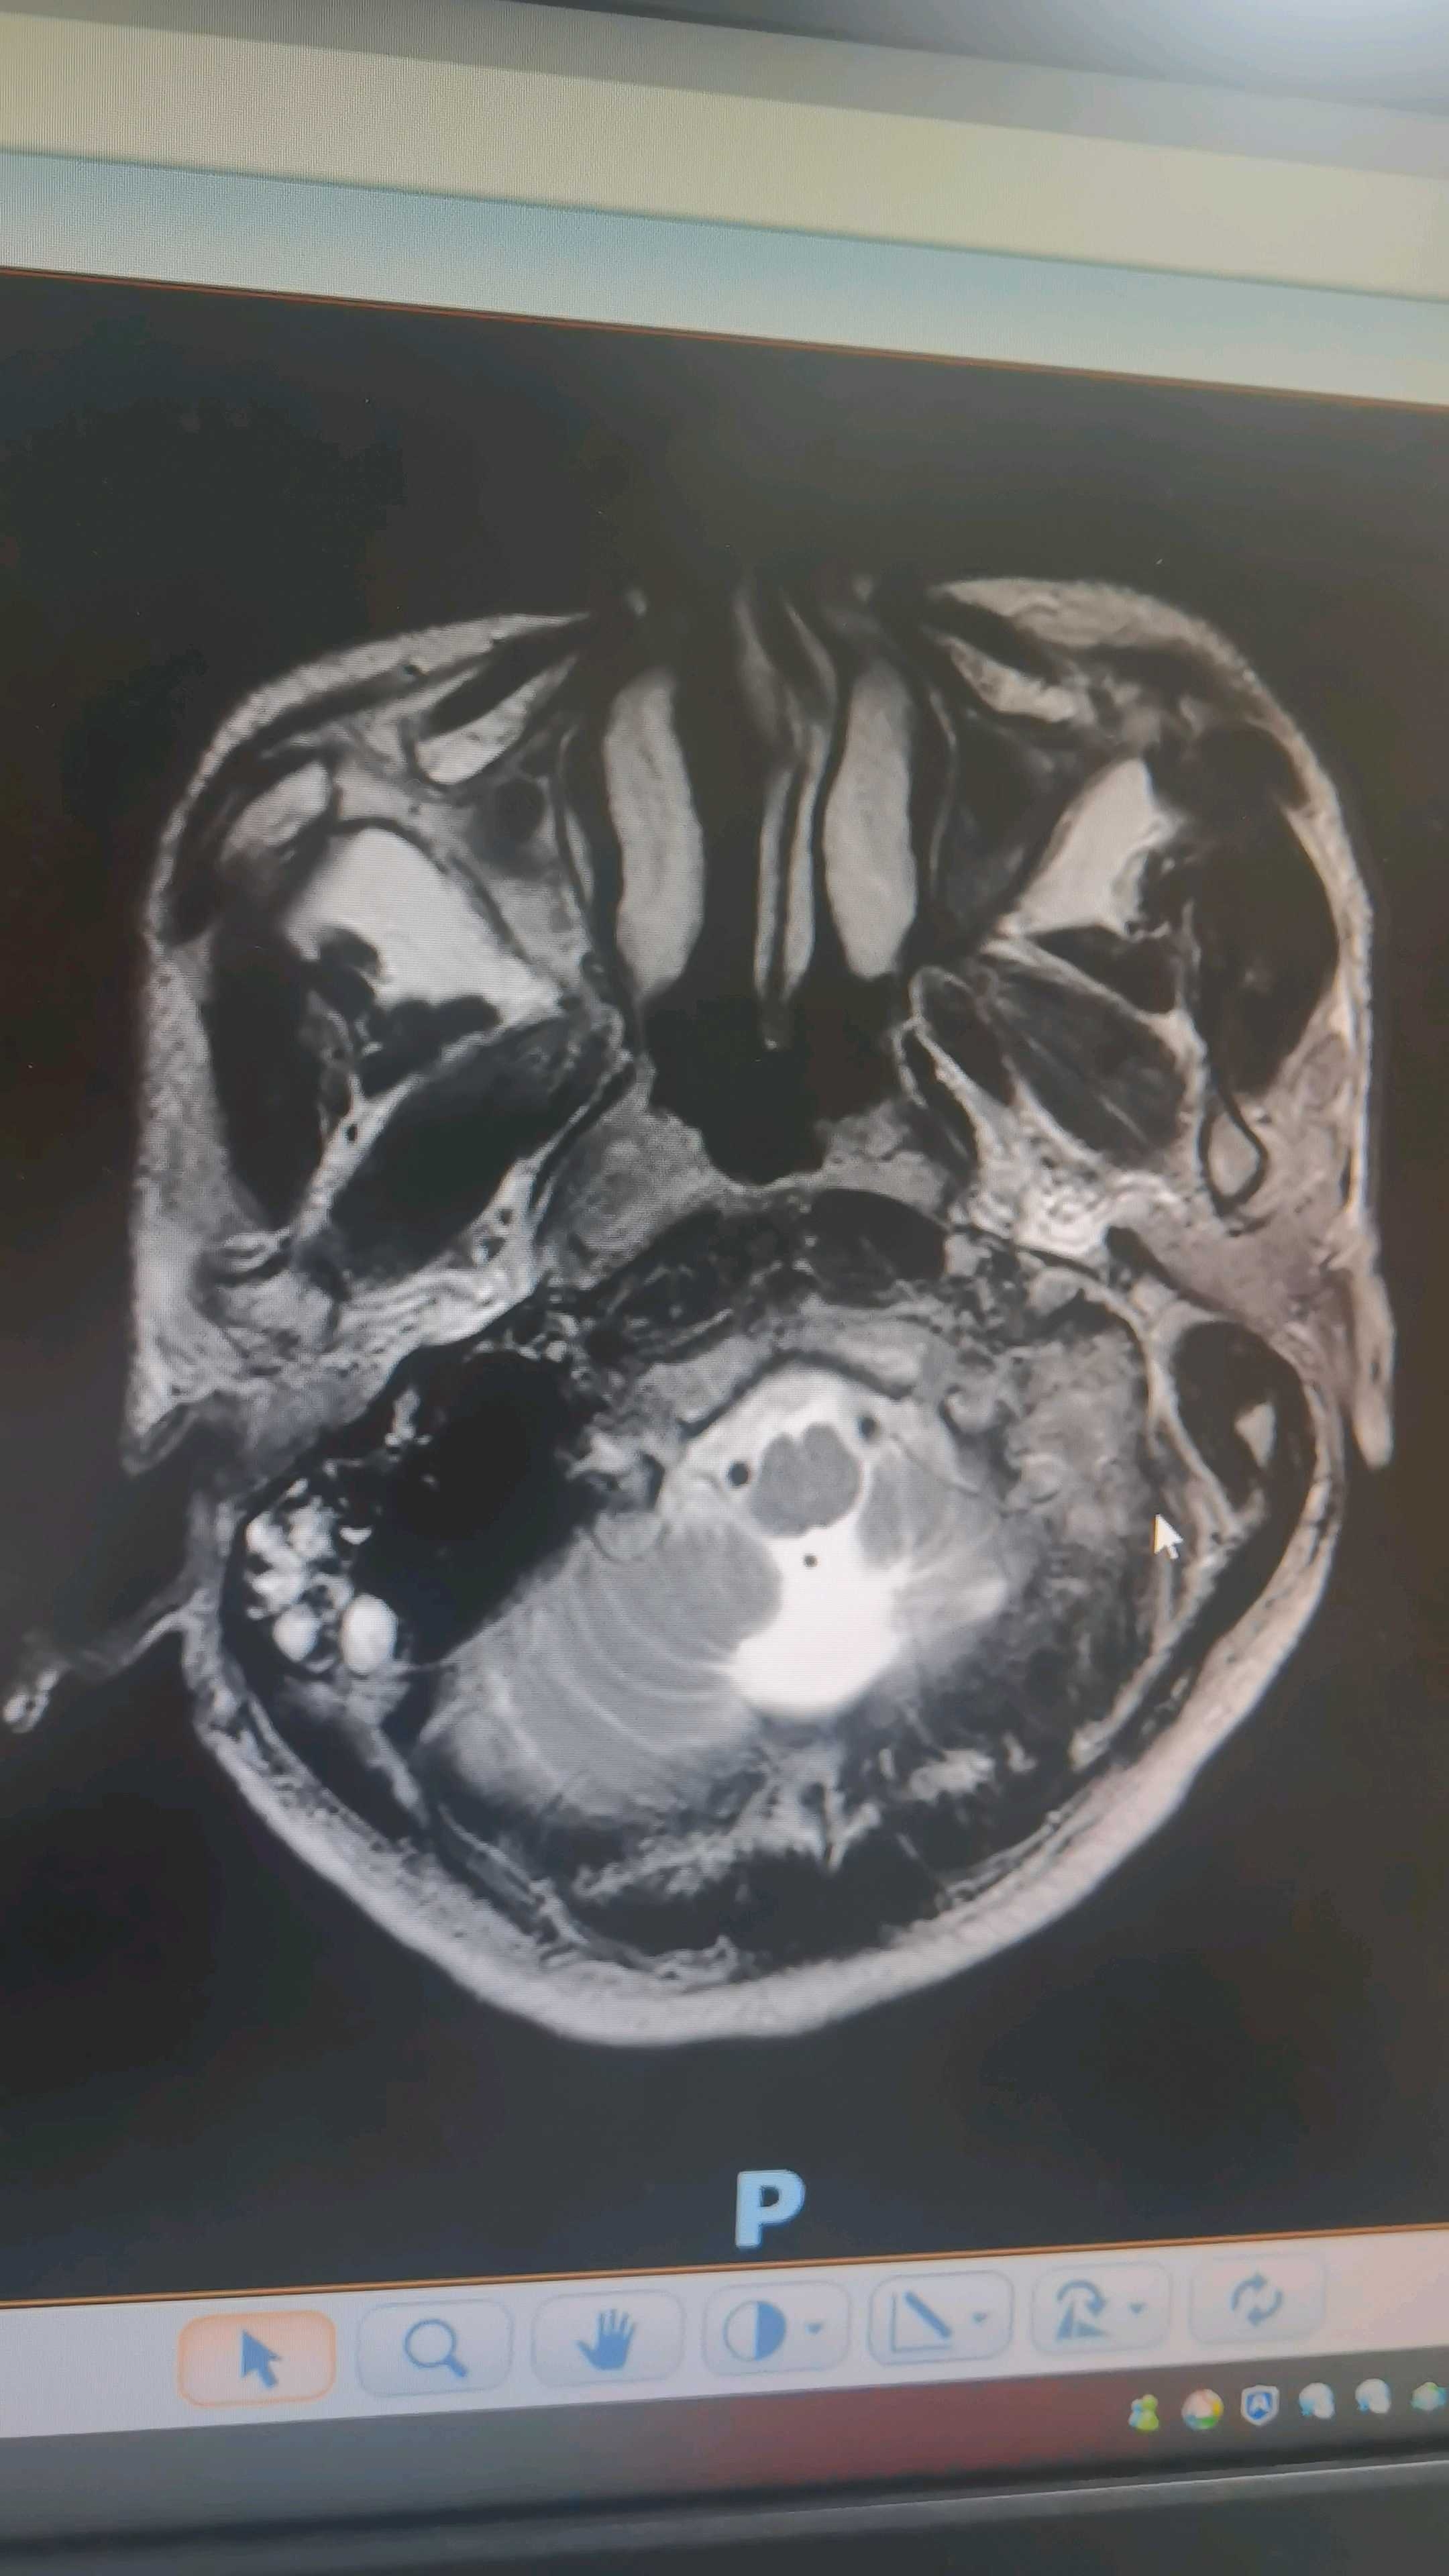

眼框mr